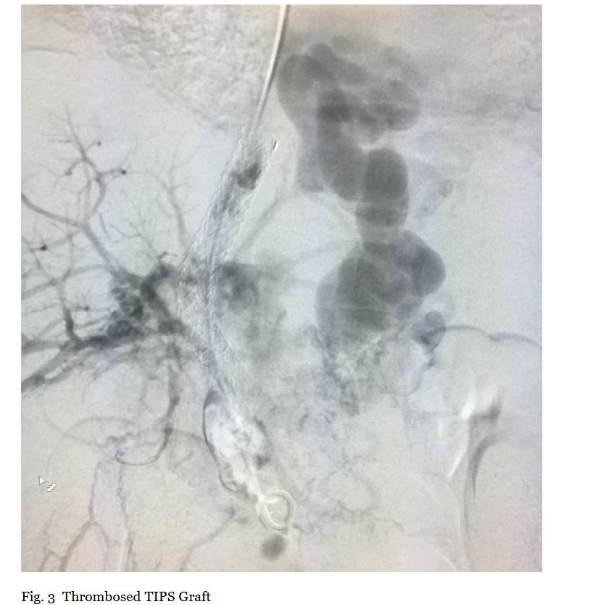

2.3.1. Initial Access, Portal Venography, and TIPS Exploration

Initial access was obtained through the right internal jugular vein under ultrasound guidance to minimize complications, followed by advancement of a 0.035-inch guidewire and 8-10 Fr sheath through pre-existing TIPS grafts. Upon reaching the portal venous system, diagnostic portal venography was performed using 10-20 mL iodinated contrast at 5 mL/s. Imaging delineated thrombus extent, morphology (e.g., occlusive vs. non-occlusive), and chronicity, with comparison to pre-procedural CT/MRI for correlation. TIPS exploration under fluoroscopy confirmed graft patency, excluding stenosis (>50% diameter reduction) that could alter strategy (Figure 3). This step was critical to quantify baseline thrombus burden (percentage occlusion via digital subtraction angiography) and guide device positioning, ensuring efficacy documentation through pre-intervention metrics.